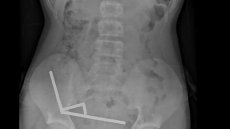

Nouvelle-Zélande: un adolescent opéré après avoir ingéré près de 100 aimants achetés sur Temu

Par AFP © 2025 AFP En Nouvelle-Zélande, un adolescent de 13 ans s'est vu retirer plusieurs parties nécrosées de ses intestins après avoir avalé près d'une centaine d'aimants achetés en ligne sur le site Temu, a rapporté vendredi une revue médicale. Après avoir souffert de douleurs abdominales (…)